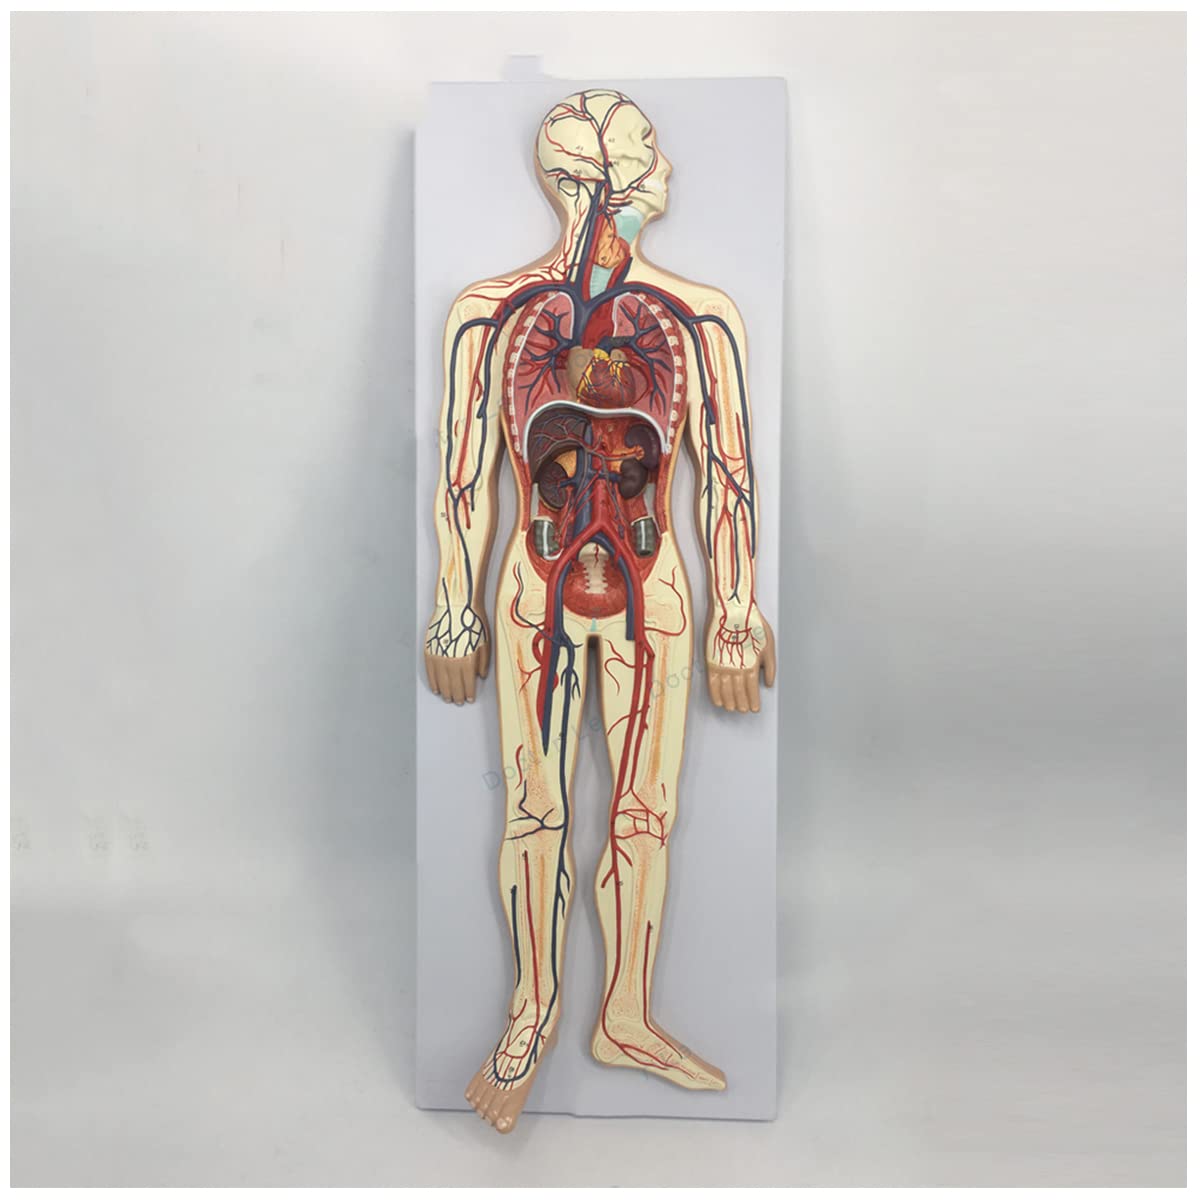

- Features: This model shows the structure of blood circulation in various parts of the human body. The circulatory system is the channel through which blood flows in the body and is divided into two parts: the cardiovascular system and the lymphatic system. Blood circulation route: superior and inferior vena cava → right atrium → right ventricle → pulmonary artery - → alveolar surrounding → pulmonary veins - >> left atrium → left ventricle → aorta - → systemic tissues (except lung). Product Size: Using this model helps to understand the composition and structure of human blood circulation. The size of the model is 1/2 the size of the human blood circulatory system. Product size: 90*30 cm/35.4*11.8 inches. High Quality: High-quality prototypes, sturdy hand-made, not fragile, made of high-quality environmentally friendly PVC, fine workmanship, creating good objects with clear shapes and rich details. Meticulous workmanship: The model has meticulous workmanship, realistic details, clear texture, easy to use and easy to observe. This product comes with a base, which is convenient for learning and teaching. Good Teaching Aids: This collection is designed for anatomy professionals and students. We are sure you will love these models. Can also be given as a gift to educators or doctors, excellent educational tool for students/teachers/professionals.

Product Specifications:Product name: Human Blood Circulatory System Model Product Type: Medical Teaching Model Product material: PVCProduct use: medicine, school, hospital, medical giftPackage list:Human Blood Circulatory System Model *1Notice:The monitor calibration is different, and the color of the object shown in the photo may be slightly different from the actual product. Please refer to the actual product.